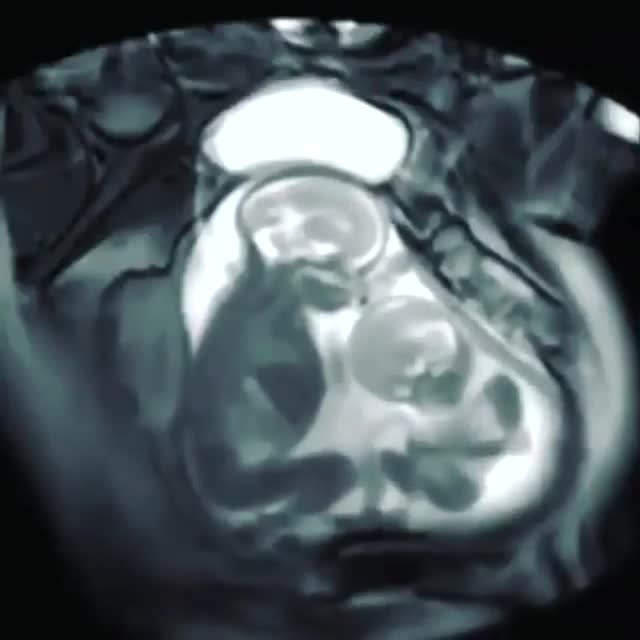

👶👶 نمای منحصر به فرد MRI از دوقلوهای همسان که تقریبا در هفته بیست حاملگی قرار دارن و در حال لگد زدن به شکم مادر هستن😊